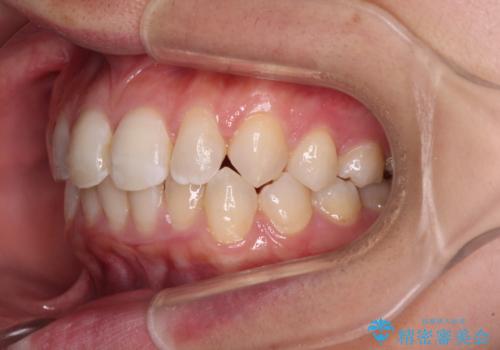

- 前歯のデコボコと歯肉に埋もれている奥歯を気にして来院された患者様です。

インビザラインでの治療を希望されていましたが、左右の下顎大臼歯が歯肉に埋もれており、特に右側は歯軸が顕著に傾斜していたため、インビザライン単独での治療は困難と判断し、ワイヤー装置を併用することとしました。

ワイヤー装置での下顎臼歯改善には時間がかかることが予想されたため、下顎のワイヤー矯正と並行して上顎をインビザラインで整え、その後インビザラインにより上下歯列を整える矯正治療を行うこととしました。